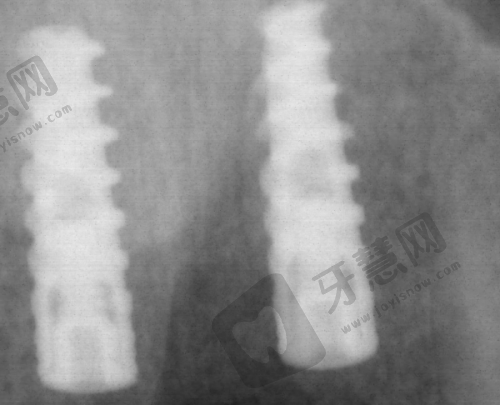

种植牙价格:韩国登腾种植牙4680元起/颗;韩国奥齿泰种植牙5560元起/颗;美国皓圣种植牙7840元起/颗;德国ICX种植牙8430元起/颗;瑞士ITI种植牙11350元起/颗;瑞典诺贝尔种植牙12780元起/颗。